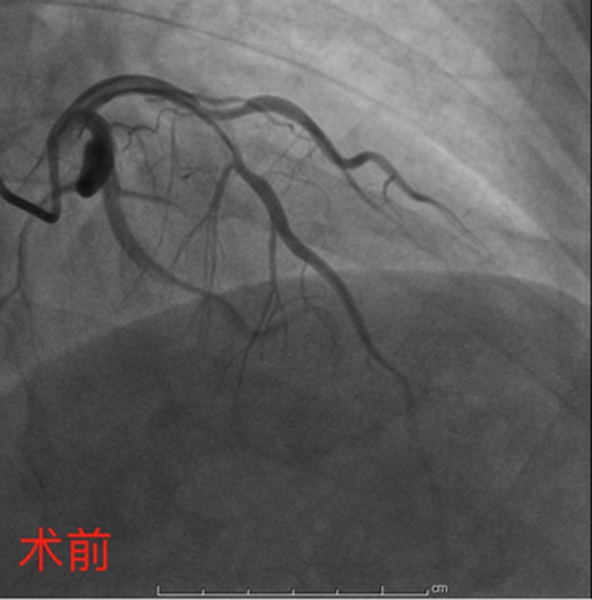

4月27日,彭道地主任与范爱德副主任医师为其手术。术中,冠脉造影提示:冠状动脉多支多处狭窄病变,其中左前降支近中段弥漫狭窄50-95%,第一对角支粗大,开口至近端狭窄75%-85%。“分叉狭窄病变”手术风险大、操作较复杂。但两位经验丰富的专家还是顺利将2枚支架植入狭窄血管,血管打通,病人病情得到明显缓解。